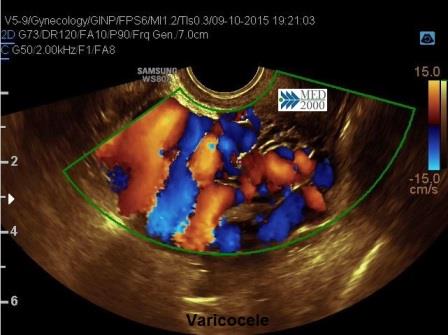

La diagnosi si avvale delle tecniche di immaging: Ecocolor-Doppler Transvaginale, TAC, RMN. In modo particolare l'ecocolor-Doppler permette di documentare la dilatazione e l'incontinenza delle vene uterine ed ovariche.